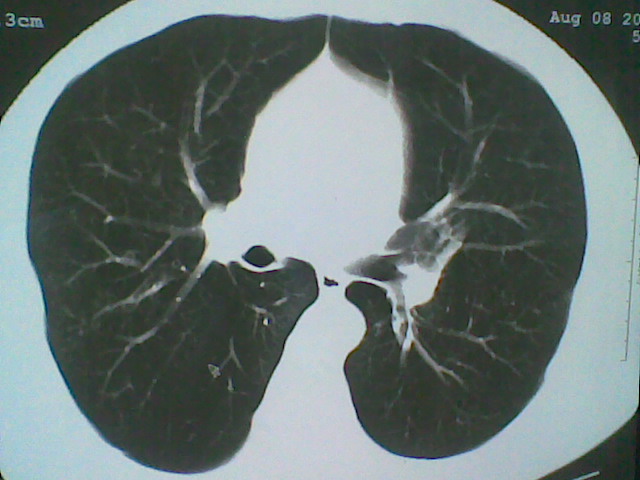

支持 支气管扩张并感染。

支持楼主意见,考虑支气管扩张并感染。

支气管扩张并感染。